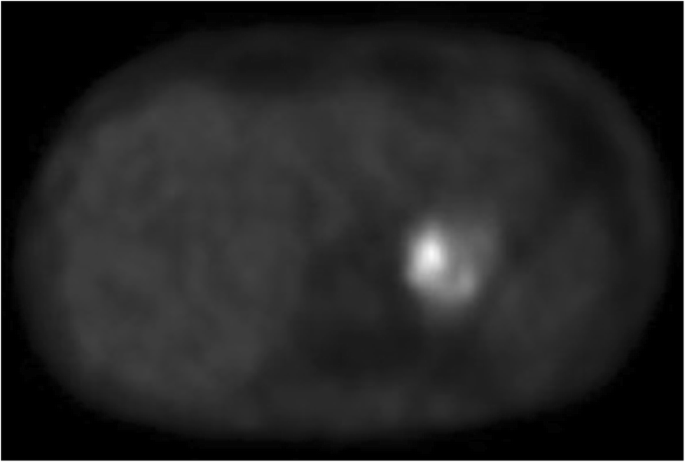

Urine analysis confirmed the hypothesis that norepinephrine levels were particularly elevated with respect to epinephrine. The patient then underwent a [123I]-MIBG to formalize the diagnosis of left-sided adrenal pheochromocytoma (Fig. 2) extending to the ipsilateral kidney.

Since [123I]-MIBG scans have inferior sensitivity for pheochromocytoma metastases [6] and the disease was high-grade, a confirmatory [18F]-DOPA PET scan was also performed as soon as the patient was extubated. Both studies showed no uptake by the vertebral lesions, whereas the primary tumor had consistently increased signal.